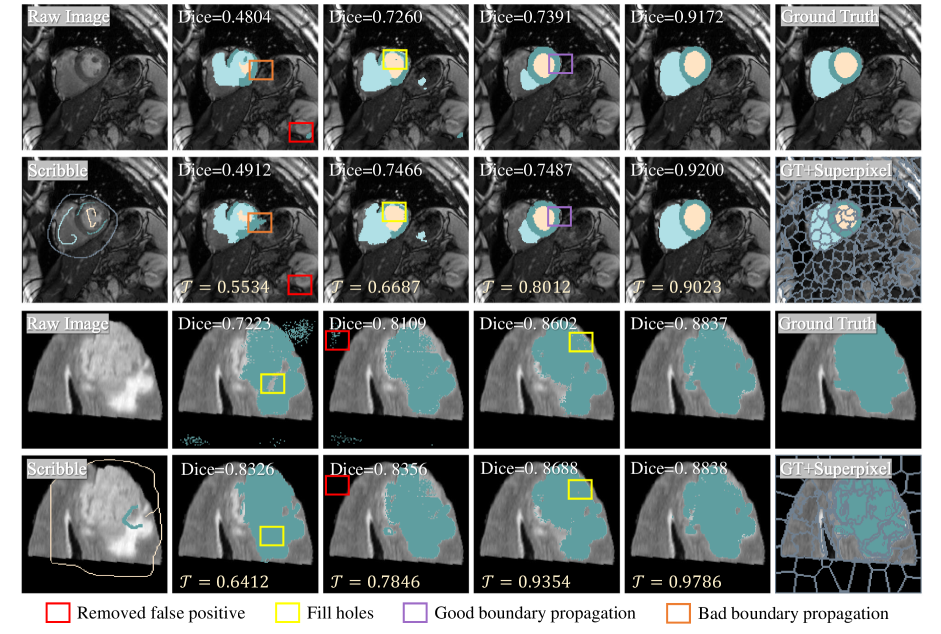

Refer to caption

Figure 6: Qualitative analysis of pseudo label refinement during iteration on two datasets. Upper rows is the original predictions and the lower rows show the refined pseudo label. 𝒯𝒯\mathcal{T} is the class-averaged threshold.

Convergence: In Figure 5(a), we explored the effects of different modules with only Dlsubscript𝐷𝑙D_{l} for training. We can observe that supervision with expanded scribbles and refined pseudo-labels both improves the convergence speed. This is primarily due to regional information provided by expanded scribble, and the supervision of the entire image region by the complete pseudo-label facilitating the learning of complete structural appearance. The supervision guided by superpixel-level uncertainty also contributes to more stable early-stage learning and aids in improving performance by focusing on high-quality regions during training. In Figure 5(b), our method converges faster than the consistency-based SOUSA method, since our method accelerates segmentation learning by providing denser labels directly.

Dynamic thresholding: We present the comparison of threshold and sampling rates in iteration in Figures 5(c) and 5(d). At the beginning of training, the threshold is set low to introduce as much potentially accurate superpixel information as possible. As performance improves, the threshold adaptively increases to filter out noisy superpixels and reduce biases. Additionally, we illustrate the sampling rate with a fixed threshold as a reference. The fixed threshold corresponds to a sampling rate that quickly converges to around 50%. The dynamic threshold adjusts based on the overall learning state with the sampling rate converging to 10% ultimately.

Refinement effect: The refinement with superpixels filtered by the dynamic threshold can help the model generate better pseudo labels during iterations, as depicted in Figure 6. As the iteration proceeds, the generated pseudo-labels get closer to the ground truth. Utilizing superpixels helps to eliminate false positive predictions and fills holes in pseudo labels. By employing dynamic thresholds for superpixel selection, we filter out bad superpixels and only use higher-quality superpixels for refinement, facilitating the propagation of favorable boundary information throughout the network. When the accuracy of pseudo-labels increases, the dynamic threshold also increases continuously causing fewer relabeling operations.